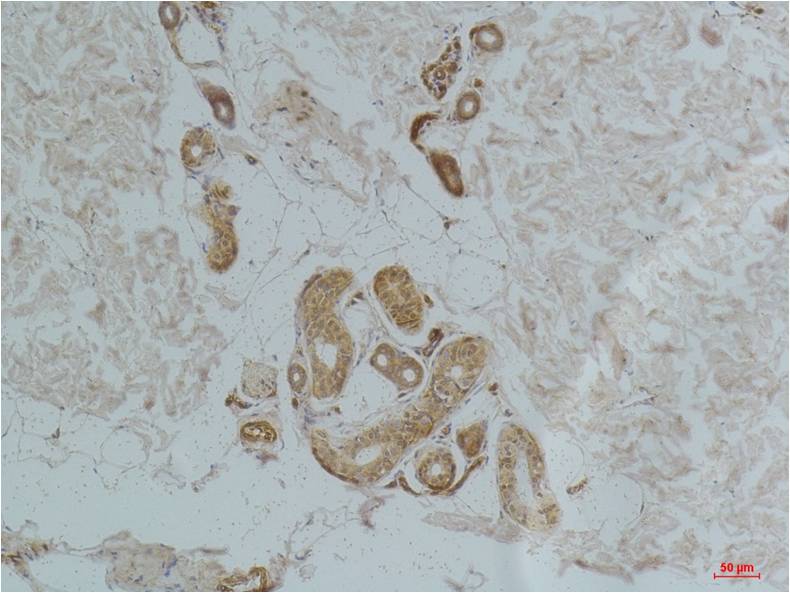

Immunohistochemical analysis of paraffin-embedded Human BrainTissue using Ghrelin Receptor (EA292)Rabbit pAb diluted at 1:200.

Immunohistochemical analysis of paraffin-embedded Human Skin Tissue using Ghrelin Receptor (EA292)Rabbit pAb diluted at 1:200.